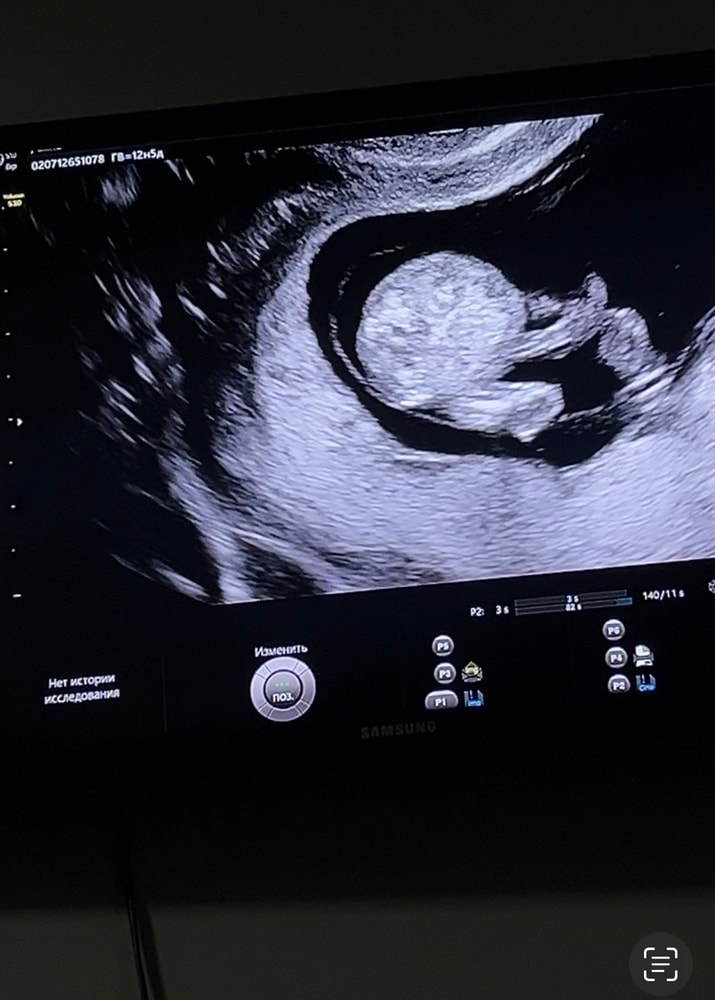

По узи срок 13 недель. 3 фотка предположили, что мальчиковые половые органы, на 1/2 фотке ничего вроде бы не видно(только пуповина). Как думаете узист ошиблась? Хотя уверена вроде говорила… Оч хочу дочу, снилась мне вчера, а тут я ошарашена новостью. Девочка до беременности снилась и я прям чувствовала, что мне надо за ней. Решилась как видите на 1 беременность и тут такое. У вас путали с пуповиной пол? Поделитесь своими историями…

Это не тот ракурс, в котором можно на вашем сроке определить пол- на вашем сроке его определяют только предположительно по направлению полового бугорка относительно позвоночника. А сам размер и форма бугорка и половых складок еще одинаковы у мальчика и девочки.